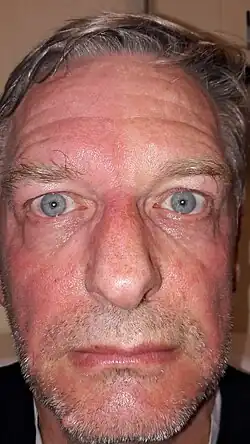

| A man exhibiting the asymmetric symptoms of Harlequin syndrome. One half of the forehead is more red than the other. | |

Harlequin syndrome, also known as "harlequin sign", is a condition characterized by asymmetric sweating and flushing on the upper thoracic region of the chest, neck and face. Harlequin syndrome is considered an injury to the autonomic nervous system (ANS). The ANS controls some of the body's natural processes such as sweating, skin flushing and pupil response to stimuli.[1] Individuals with this syndrome have an absence of sweat skin flushing unilaterally, usually on one side of the face, arms and chest. It is an autonomic disorder that may occur at any age.[2]

Symptoms associated with Harlequin syndrome are more likely to appear under the following conditions: vigorous exercise, warm environments and intense emotional situations. Since one side of the body sweats and flushes appropriately to the condition, the other side of the body will have an absence of such symptoms.[3]